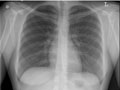

Chest X-Ray

A chest X-ray is a picture of the chest that shows your heart, lungs, airway, blood vessels, and lymph nodes. A chest X-ray also shows the bones of your spine and chest, including your breastbone, your ribs, your collarbone, and the upper part of your spine.

A chest X-ray can help find some problems with the organs and structures inside the chest. Usually two pictures are taken, one from the back of the chest and another from the side. In an emergency when only one X-ray picture is taken, a front view is usually done. Doctors may not always get the information they need from a chest X-ray to find the cause of a problem. If the results from a chest X-ray are not normal or do not give enough information about the chest problem, more specific X-rays or other tests may be done, such as a computed tomography (CT) scan, an ultrasound, an echocardiogram, or an MRI scan.